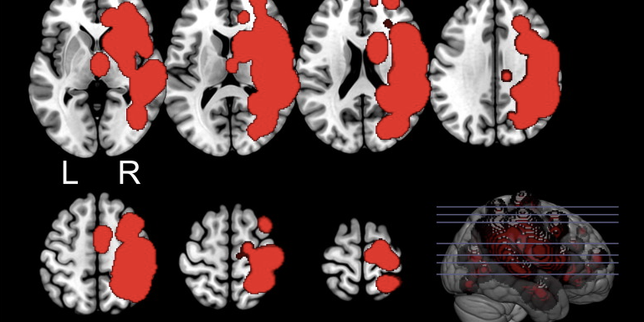

© Saetta G, et al. Neuroscience. 2021 Nov 10 ;476 :21-33.